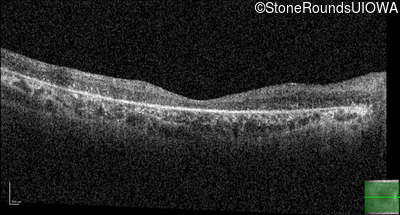

Optical Coherence Tomography - Left - 10/180 sc

Exemplar / OCT Stack